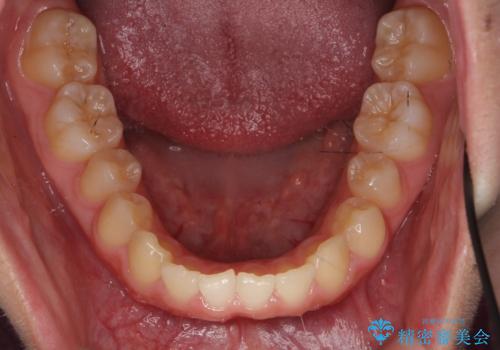

- 前歯の並びを主訴に来院。

また、右の奥歯の関係も上が前にある状態で大きくずれていました。

臼歯関係は無理に1級にしようとすると抜歯が必要になります。

今回は左右とも1歯対2歯の関係であるため、それは変えずに前歯を可及的にひっこめて足りない部分をブリッジで補う治療としました。

奥歯の関係を完全に1級にするには右上の小臼歯の抜歯が必要でしたが、もともと左上の前歯が生まれつき少ないため今回は歯を抜かずに治療しています。